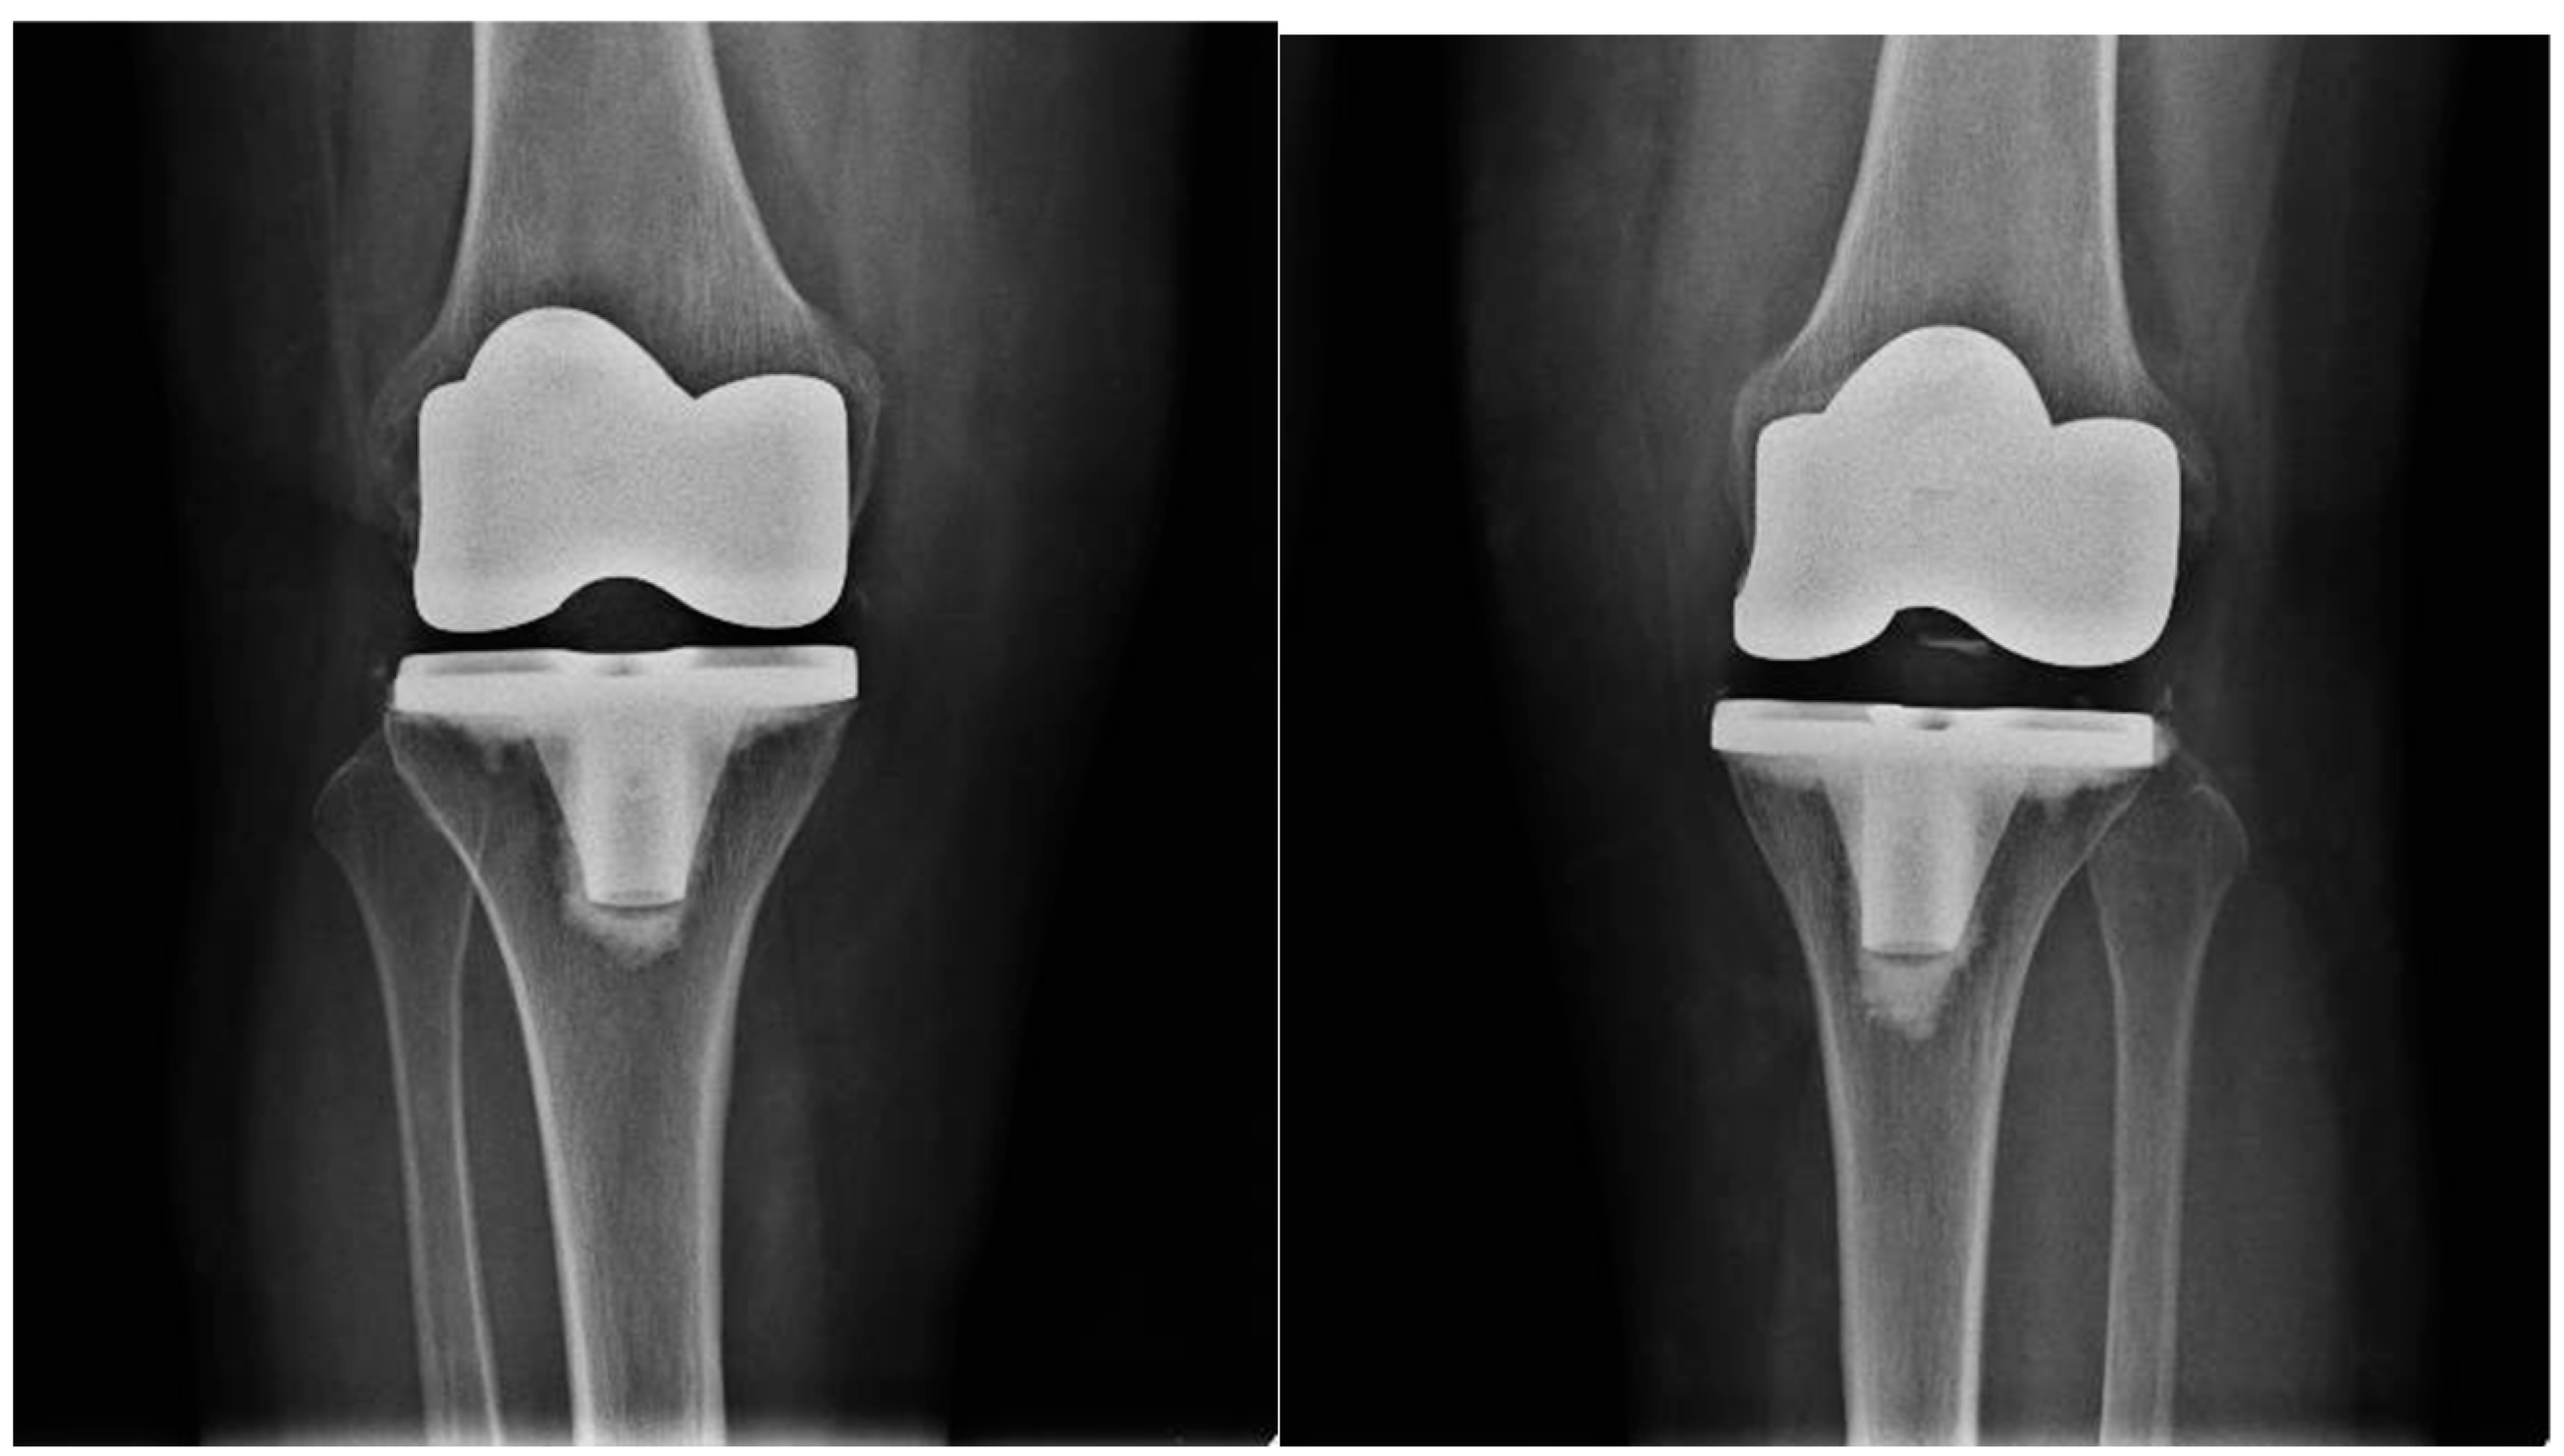

Antibiotic prophylaxis with cefazolin was used. All patients underwent radiographs (Figure 2) in the immediate postoperative period.

Figure 2. Postoperative radiography of bilateral total knee arthroplasty.